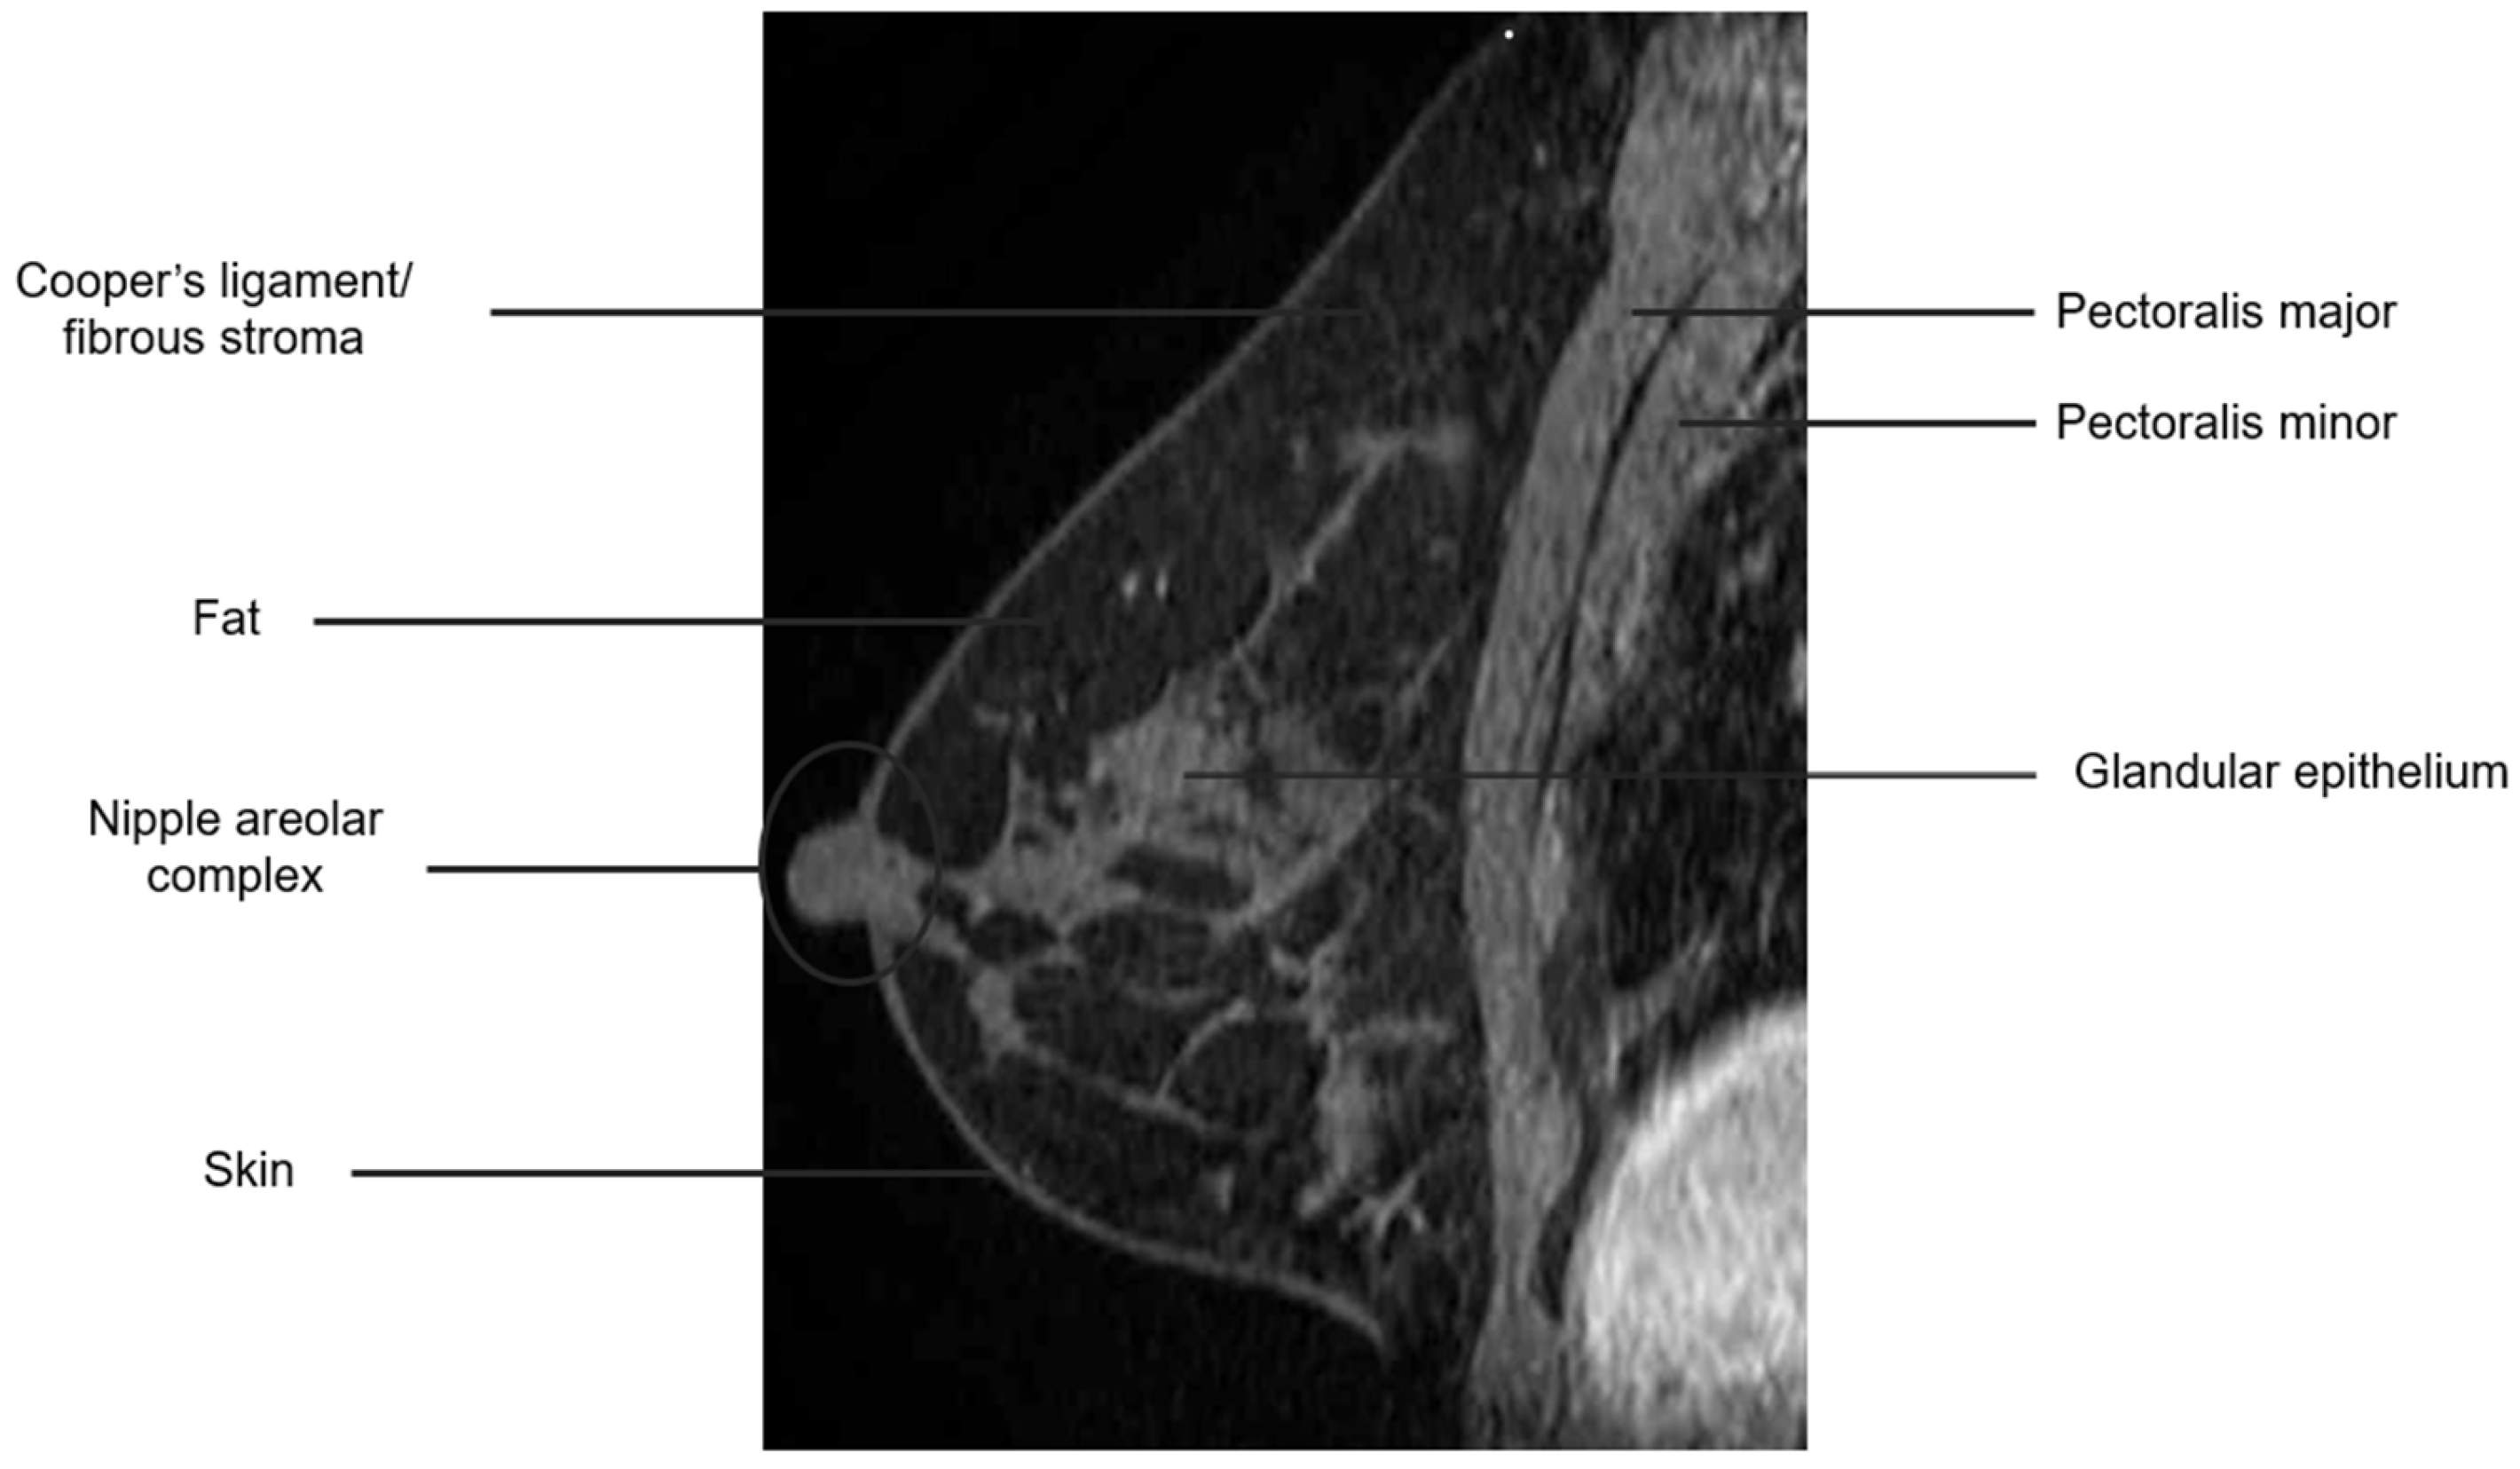

The breast is composed of glandular epithelium, fibrous stroma, and fat. The glandular epithelium in the breast consists of two main building blocks: ducts and lobules. Together, the ducts and lobules form ductal-lobular units, which coalesce to form approximately 15–20 lobes in a breast. Each lobe leads to a duct that widens to form a lactiferous sinus under the nipple–areolar complex prior to exiting the nipple. The fibrous stroma—frequently referred to as Cooper’s ligaments—is composed of bands of connective tissue that traverse the breast and insert into the dermis. These basic structures are seen at breast MRI (Figure 3). The amount of fibroglandular tissue (FGT) is evaluated on T1-weighted (either on the fat-saturated or non-fat-saturated) breast MR imaging sequences (Figure 4) [35].

Figure 3.

Anatomy of the breast on a sagittal T1W fat-suppressed post-contrast breast MRI.